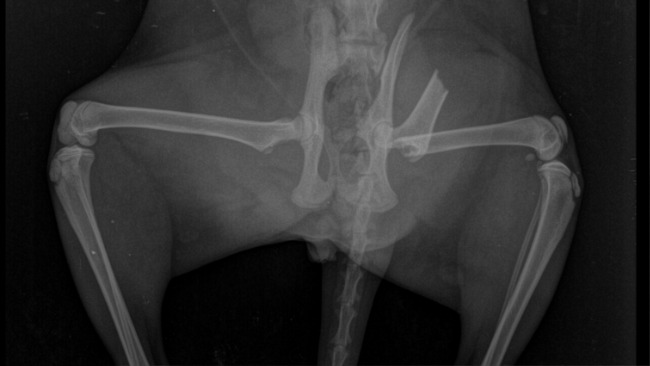

Niestety w zeszłym tygodniu w nocy z piątku na sobotę stała się tragedia... Młodego najprawdopodobniej uderzył samochód. Po wypadku na całe szczęście doczłapał się po schodach na taras mojego domu. O godzinie 6 rano w sobotę wpuściłam kotki do domu, aby je nakarmić. Młody ostatkiem sił wszedł do domu, ale już się więcej nie poruszył. Zobaczyłam wtedy, że obydwie tylne nogi ma z jednej strony i nie może chodzić, piszczał z bólu, jak tylko próbowało się go tam dotknąć. Zaraz w sobotę został przewieziony do weterynarza. W poniedziałek diagnoza - złamanie z przemieszczeniem prawej kości udowej i podejrzenie złamania/zwichnięcia stawu biodrowo-krzyżowego. Niżej zamieszczam zdjęcia z prześwietlenia.

Z racji, że Młody był kotem wolnożyjącym liczyłam się z tym, że Gmina może podjąć decyzję o uśpieniu kotka. Za nic nie mogłam na to pozwolić, nie mogłam zawieść Młodego. W środę był operowany. Operacja się udała. Młody po operacji przebywa u mnie w domu, ma swój pokój, gdzie ma zapewnioną ciszę, ciepło i opiekę. Na zdjęciach widać zamontowany stabilizator zewnętrzny.